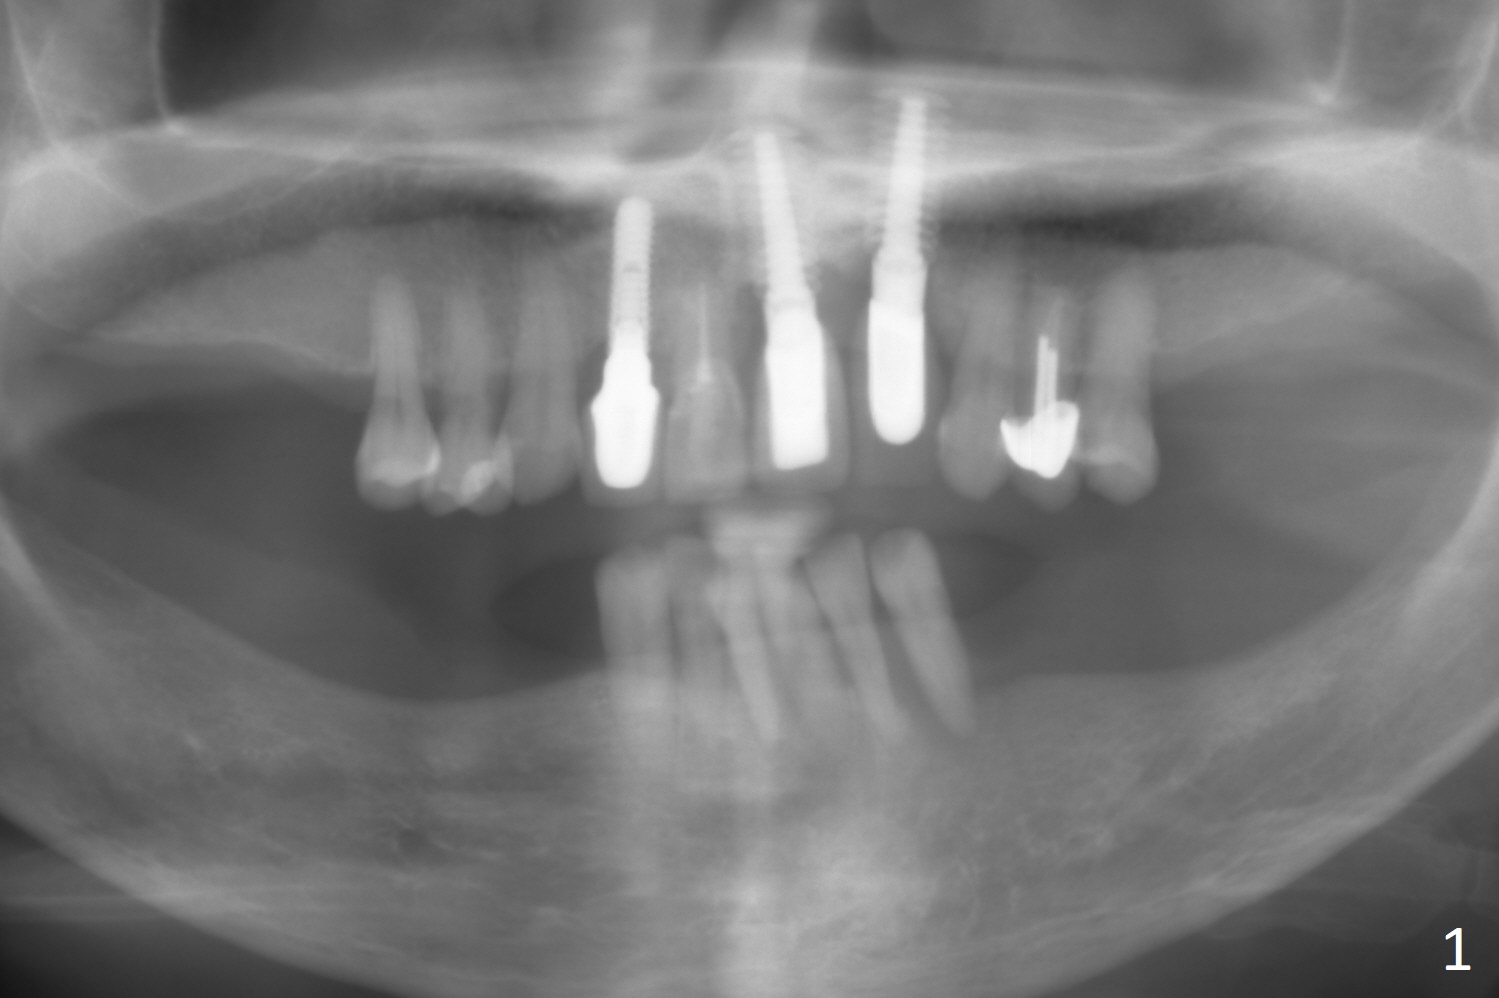

A 71-year-old woman is skinny with multiple missing teeth (Fig.1). Our final plan is to establish premolar occlusion. The first aim is to place implants at #22 and 23 with severe mobility and gingival recession (Fig.2). The latter is most likely due to traumatic occlusion from #10 implant crown. Pay attention to occlusion while an immediate provisional is being fabricated. After extraction, trajectory should be set up as shown by red lines in Fig.3. Initiate osteotomy in the middle of the sockets (buccolingually) and use the narrowest implants (2.5, 3.5 mm) to avoid the lingual plate perforation. Take preop photos to show #9,10 gingival recession.